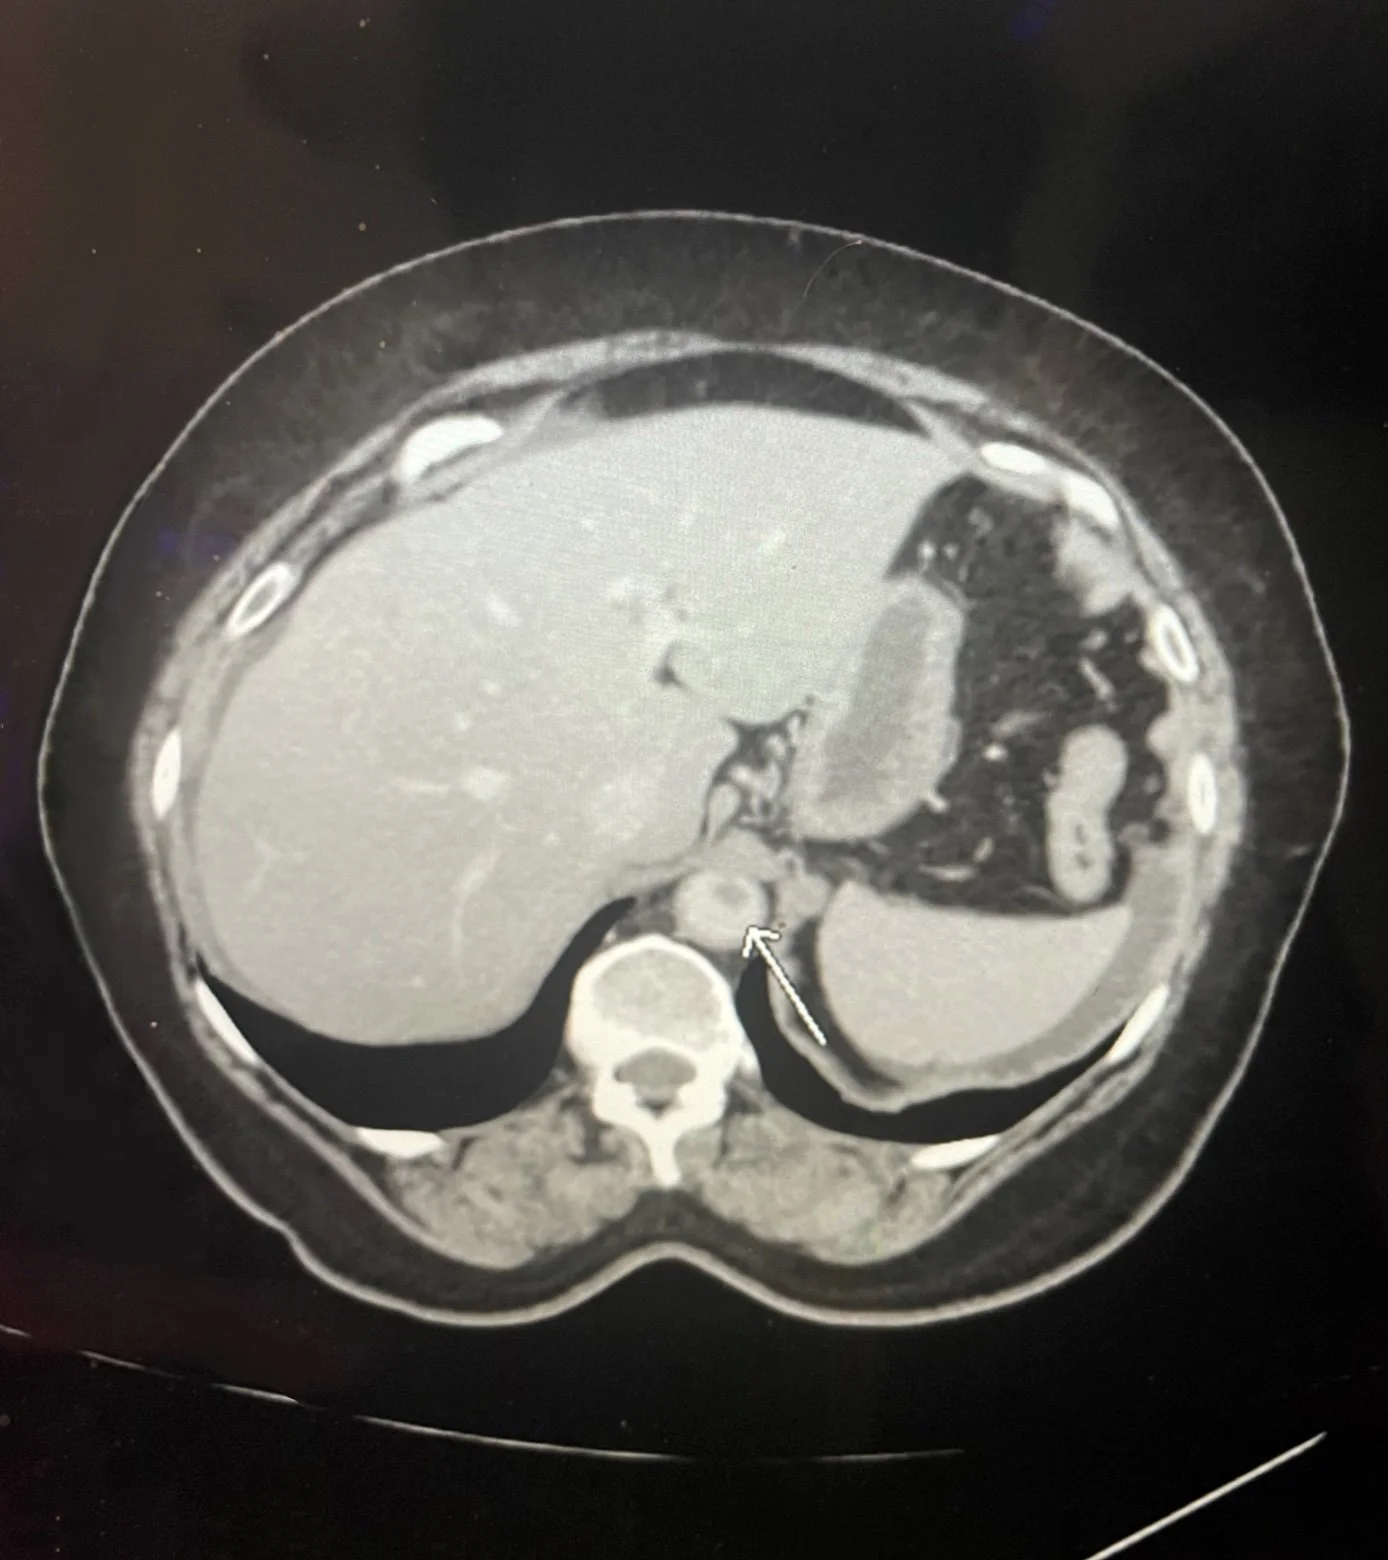

Aortic reconstruction is a major vascular surgery used to repair the aorta, the body’s largest artery, when it becomes damaged by an aneurysm (bulging) or occlusive disease (blockage). This procedure is performed through an open surgical approach to allow for a direct reconstruction of the affected aortic segment.

Endovascular Aneurysm Repair (EVAR) is a minimally invasive procedure that can be used to manage abdominal aortic aneurysms. EVAR uses small punctures and complex instruments to repair the bulges in the blood vessels (aneurysms). Left untreated, this can be a life-threatening condition. It is minimally invasive, requires a shorter hospital stay, and has a lower risk of complications.